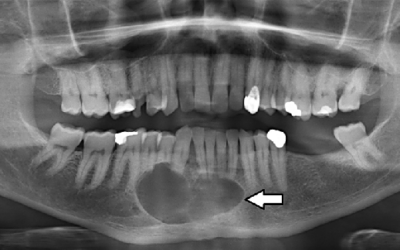

Το αδαμαντινοβλάστωμα είναι ένας σπάνιος, καλοήθης όγκος που προέρχεται από τα κύτταρα που σχηματίζουν την αδαμαντίνη (σμάλτο) των δοντιών. Εμφανίζεται κυρίως στη γνάθο και, παρά τη μη κακοήθη φύση του, μπορεί να οδηγήσει σε σημαντικά προβλήματα αν δεν αντιμετωπιστεί...